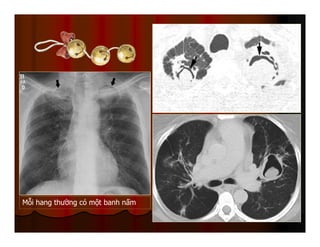

Mỗi hang thường có một banh nấm

DẤU HIỆU LỤC LẠC

(SIGN OF TINTINNABULUM)

Sign of tintinnabulum = Signe de grelot.

Nấm Aspergillus có thể gây bệnh ở người với 2 thể chính:

Thể xâm lấn mạch máu (Angioinvasive Aspergillosis): tổn

thương lan toả, gặp ở người có cơ địa suy giảm miễn dịch. Ở

thể này ta có dấu hiệu vầng hào quang (halo sign) trên CT.

Thể banh nấm (Saprophytic Aspergillosis = Aspergilloma):

hình thành banh nấm (fungus ball) trong lòng các tổn thương

hang ở phổi, thường gặp ở BN có hang lao. Thể này cho dấu

hiệu lục lạc (Tintinnabulum sign) hay dấu hiệu liềm khí (Air

crescent sign) tuỳ theo tác giả.

Mỗi hang thườngcó một banh nấm

DẤU HIỆU LỤCLẠC (SIGN OF TINTINNABULUM) Sign of tintinnabulum = Signe de grelot. Nấm Aspergillus có thể gây bệnh ở người với 2 thể chính: Thể xâm lấn mạch máu (Angioinvasive Aspergillosis): tổn thương lan toả, gặp ở người có cơ địa suy giảm miễn dịch. Ở thể này ta có dấu hiệu vầng hào quang (halo sign) trên CT. Thể banh nấm (Saprophytic Aspergillosis = Aspergilloma): hình thành banh nấm (fungus ball) trong lòng các tổn thương hang ở phổi, thường gặp ở BN có hang lao. Thể này cho dấu hiệu lục lạc (Tintinnabulum sign) hay dấu hiệu liềm khí (Air crescent sign) tuỳ theo tác giả.